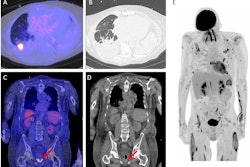

These drugs are now widely prescribed for individuals with type 2 diabetes and for weight loss -- with a 700% use increase in the U.S. between 2019 and 2023. They alter glucose metabolism, gastric motility, and sympathetic tone, which may lead to unique uptake patterns on PET-CT, noted a team led by Peter Strouhal, MD, PhD, medical director of U.K.-based imaging services provider Alliance Medical. Previous research has suggested that GLP-1 receptor agonists increase FDG uptake in skeletal muscle, the myocardium, and brown adipose tissue -- imaging results that could be mistaken for malignancy or inflammatory disease.